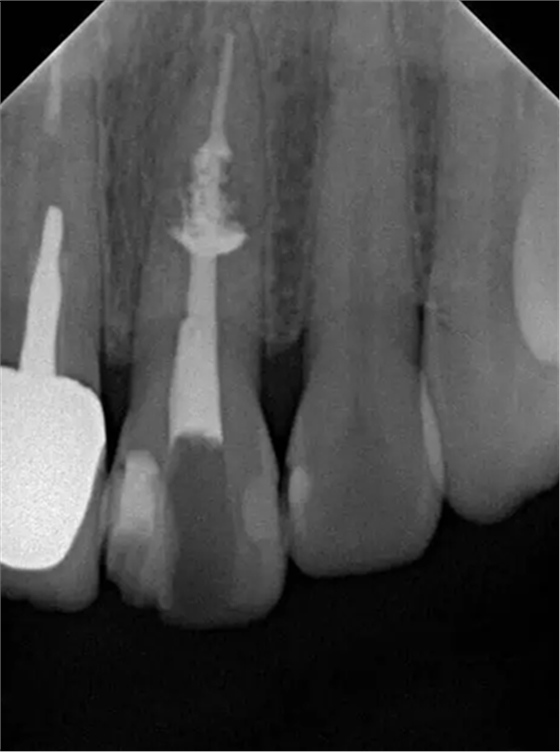

診斷:左上中切牙牙根內(nèi)吸收。治療計劃:左上中切牙根管治療,全冠修復。 治療過程:患者知情同意。使用含1/100,000腎上腺素的4%鹽酸阿替卡因(碧蘭麻,艾龍)局部浸潤麻醉,橡皮障隔濕。去腐未盡露髓,露髓孔出血多。開髓,使用10#不銹鋼K銼(MANI,日本)探查根管,根管中段有鈣化物阻擋,不能達到牙根全長(圖3A)。在顯微鏡下(Leica M400E,萊卡, 德國) 使用超聲尖(E1根管治療超聲尖,啄木鳥公司,中國)通開,采用根管長度測量儀(Root ZX, Morita公司,日本)加診斷絲片法(圖1B)測量根管長22 mm。使用控制扭矩馬達(X-smart,登士柏)和鎳鈦旋轉器械(Hero 642, Micromega)根管預備,根管預備過程中使用5.25%次氯酸鈉溶液沖洗。 根備完成后使用超聲蕩洗根管,5.25%次氯酸鈉溶液3 分鐘, 17% EDTA溶液1分鐘。干燥根管,使用螺旋充填器根管內(nèi)封氫氧化鈣糊,氧化鋅丁香油水門汀暫封。1周后患者復診,患者述無術后不適,檢查暫封完好,無叩痛,不松,牙齦無紅腫瘺管。使用橡皮障隔濕,去除暫封物,超聲蕩洗根管,5.25%次氯酸鈉溶液3 分鐘, 17% EDTA溶液1分鐘。干燥根管,牙膠尖(達雅鼎,中國)和必蘭根充糊劑(Cortisomol, 艾龍公司,法國)熱垂直加壓法根管充填。術后片顯示根充恰填,可見牙膠/糊劑被壓入鈣化物周圍和內(nèi)部縫隙內(nèi)